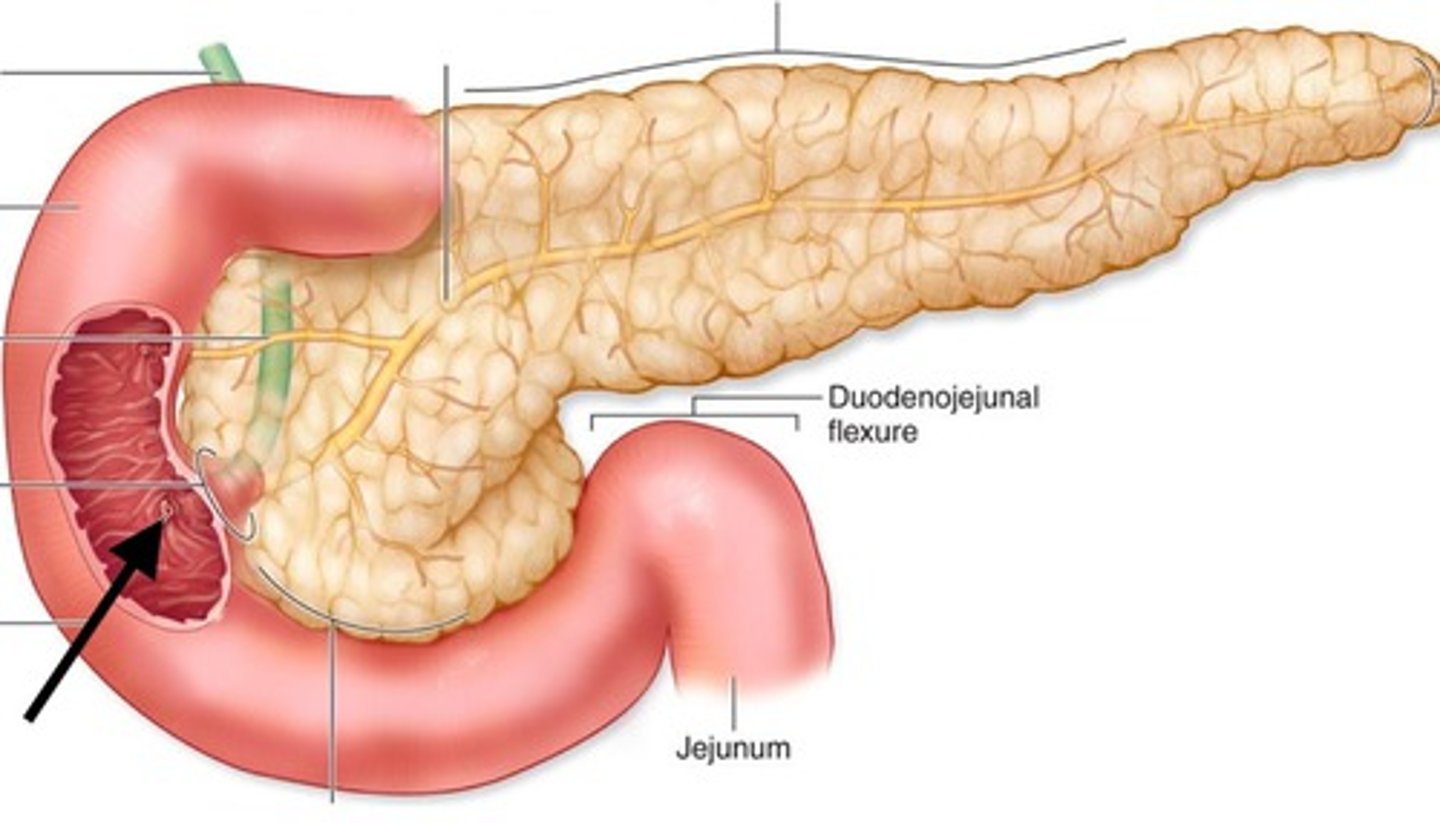

duodenum

major duodenal papilla

opening of ampulla into duodenum

circular folds (duodenum)

head (of pancreas)

main pancreatic duct

accessory pancreatic duct

hepatopancreatic ampulla

pancreatic + bile duct

duodenojejunal junction